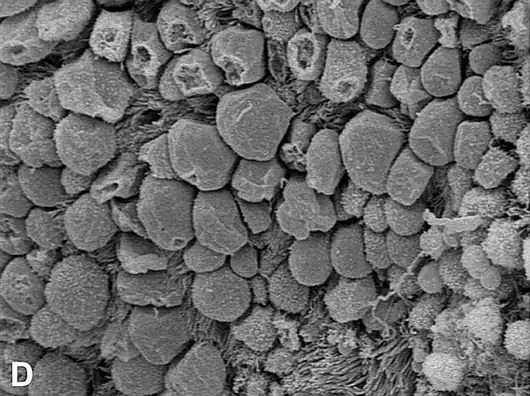

El epitelio del pabellón está conformado por células secretoras y células ciliadas. La motilidad de estas cilias es esencial para la captación del óvulo y por tanto para la fertilidad.

Internamente, cada oviducto está cubierto de una mucosa con pliegues ("plicas"), con un epitelio cilíndrico pseudoestratificado con células ciliadas, células caliciformes y células no ciliadas intercalares (o peg). Las células epiteliales descansan sobre una lámina basal y una lámina propia conjuntiva laxa subyacente.

Los cilios, ayudan a movilizar al ovocito y a su encuentro con los espermatozoides, o al cigoto para su implantación en el endometrio.

- Batido de los cilios

La actividad ciliar es responsable de la captación de óvulos por el ostium fimbrial y del movimiento a través de la ampolla, así como de la distribución del líquido tubárico que apoya la maduración y fertilización de los gametos.

Los cilios móviles funcionales presentes en el #Pabellón de la trompa, son esenciales para la recogida y el transporte de los ovocitos. Los cilios móviles en las regiones de la Ampolla y el Istmo del oviducto facilitan el transporte de gametos y embriones.[14]

Justo antes de la ovulación, las células del epitelio de la trompa uterina aumentan las cilias. Los cilios móviles del #Pabellón de la trompa, son esenciales para la recogida y el transporte de los ovocitos.[14]